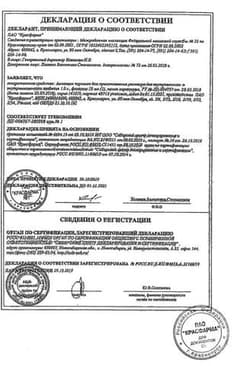

Сертификаты